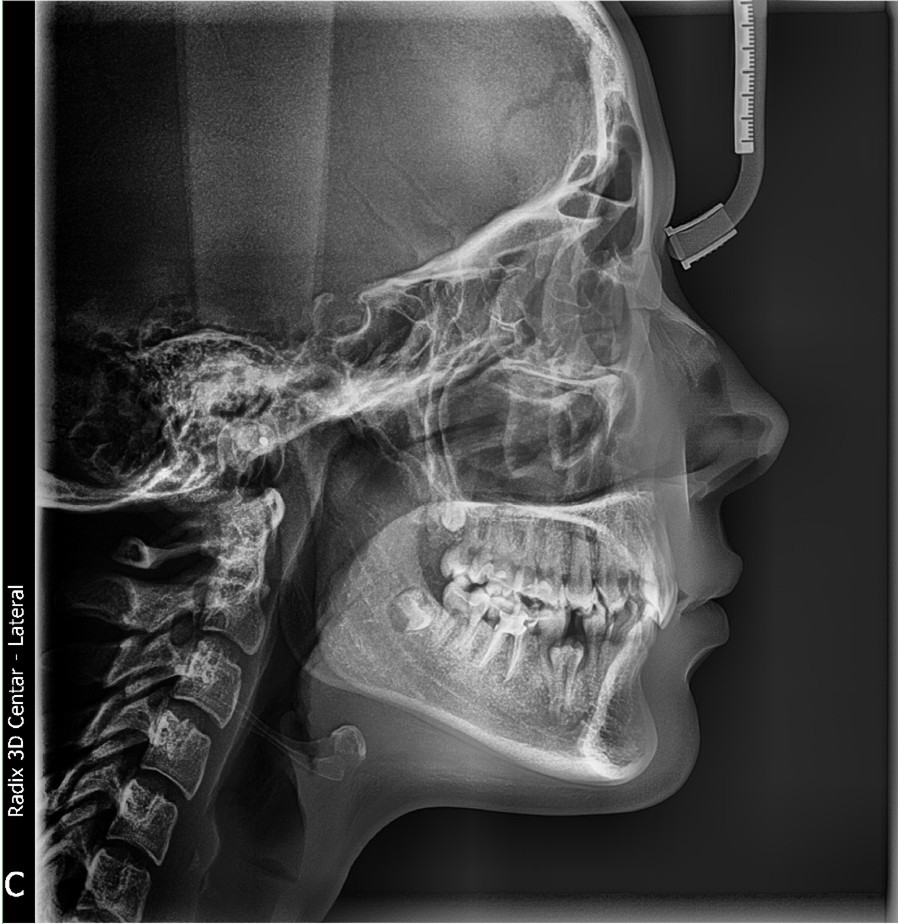

Snimci se obrađuju u EzDent i Scanora softveru, tako da se dobiju odgovarajući kontrast i prosvetljenje. Snimak se može štampati kako na foliji normalnih dimenzija ili slati e-mailom. Prednost kod elektronski poslatog snimka je što se može uvećati i prilagoditi (sve što može da se uradi i sa digitalnom fotografijom) i može lakše i neograničeno da se čuva, kao i svaki drugi fajl a prednosti štampanog snimka su specifičan proziran prikaz koji zubnom lekaru daje bolji osećaj „dubine" projekcije i mogućnost premeravanja i obeležavanja što je od posebne važnosti za profilni kefalogram u ortodonciji.

Telerendgen je lateralni (bočni) rendgenski snimak glave koji prikazuje kosti lica, zube i okolne strukture u profilu...